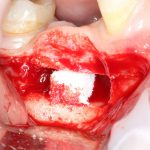

Изоляция области аутографта и имплантатов барьерной мембраной.

Перекрывать костный блок барьерной мембраной или оставить так? По этому вопросу есть много мнений. Между тем, в публикации по методике есть ясное показание, когда это требуется.

Конкретно в этом клиническом случае между костным аутотрансплантатом, ложем и имплантатами есть пустое пространство. Если его не изолировать от мягких тканей, они прорастут и осложнят интеграцию аутографта. Поэтому я решил перекрыть костный блок барьерной мембраной, пусть это делает хирургическую операцию немного дороже.

— я использовал барьерную мембрану Geistlich Bio-Gide, которая имеет две разные поверхности: с одной стороны она рыхлая «адгезивная», с другой — гладкая и прочная. Как укладывать — на результат не влияет, но в плане удобства рыхлую поверхность мы «приклеиваем» к тому, на чем требуется барьерную мембрану удержать. В данном случае хотелось бы удержать её на костной поверхности — следовательно, мы укладываем её рыхлой поверхностью к кости.

— много лет мы используем антибиотики для интраоперационной профилактики инфекционно-воспалительных осложнений. Уже в то время мы пришли к выводу, что удобнее всего — порошки антибактериальных препаратов для приготовления раствором: дешевые, стерильные, в удобной упаковке. Прямо в виде порошка их можно добавлять в графт, растворы для ирригации, либо использовать так, как показано на фото. Еще мы используем порошок антибиотика для изготовления пасты, которой обрабатываем имплантаты в процессе ревизии или при лечении периимплантита. Это удобнее и эффективнее, чем интраоперационное использование жидких форм антибактериальных препаратов.

— ты знаешь, что барьерная мембрана может выполнять две функции, каркасную и изолирующую. Первая функция требует обязательной фиксации и натяжения, вторая — нет. В нашем случае «каркасом» регенерата является костный блок, а барьерная мембрана нужна только для изоляции. Поэтому она не требует натяжения и фиксации пинами.

После я внимательно проверил, что костный блок и имплантаты полностью перекрыты. Теперь рану можно ушивать.